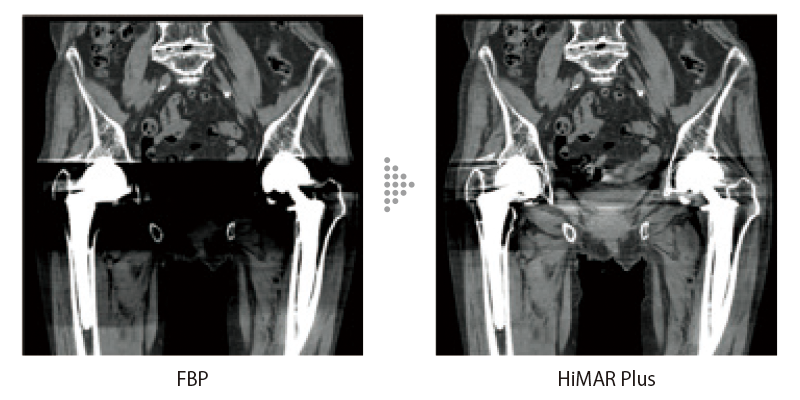

金属部分を抜き出しアーチファクトを推定し補正を行います。効果の強度が選択可能で目的に応じてご使用いただけます。AI技術を活用して開発した画像再構成技術IPV*2との併用も可能で、ノイズ低減を実現します。また、ポストリコンの時だけでなくスキャン時やマルチリコン時にも適用可能です。